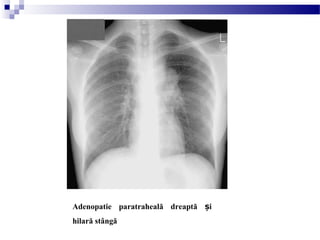

Adenopatie paratraheală dreaptă iș

hilară stângă